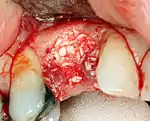

Cement peri-implantitis

Dental cement under the gingiva causes peri-implantitis and implant failure.

Long-term failures are due to either loss of bone around the tooth and/or gingiva due to peri-implantitis or a mechanical failure of the implant. Because there is no dental enamel on an implant, it does not fail due to cavities like natural teeth. While large-scale, long-term studies are scarce, several systematic reviews estimate the long-term (five to ten years) survival of dental implants at 9398 percent depending on their clinical use.[1][2][3] During initial development of implant retained teeth, all crowns were attached to the teeth with screws, but more recent advancements have allowed placement of crowns on the abutments with dental cement (akin to placing a crown on a tooth). This has created the potential for cement, that escapes from under the crown during cementation to get caught in the gingiva and create a peri-implantitis (see picture below). While the complication can occur, there does not appear to be any additional peri-implantitis in cement-retained crowns compared to screw-retained crowns overall.[68] In compound implants (two stage implants), between the actual implant and the superstructure (abutment) are gaps and cavities into which bacteria can penetrate from the oral cavity. Later these bacteria will return into the adjacent tissue and can cause periimplantitis.